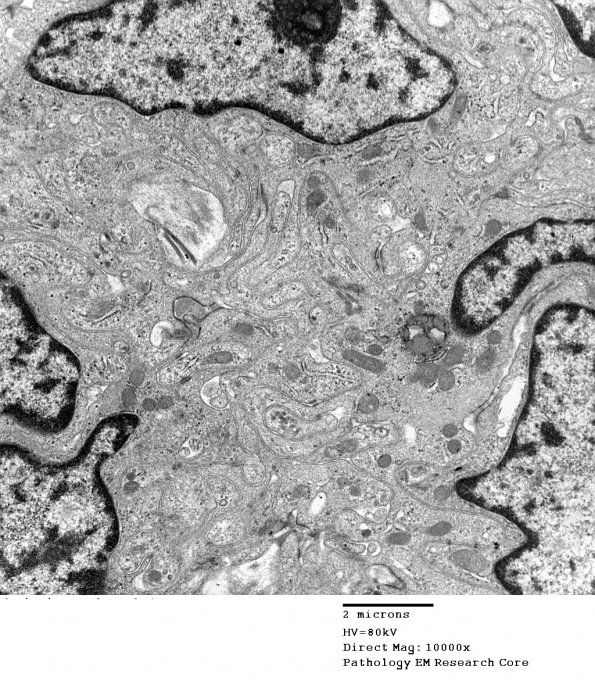

6A2,3 There are numerous junctions between processes and cell bodies (arrowheads, 6A3) (electron micrographs)